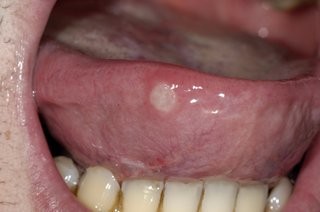

Are you prone to getting mouth ulcers? There are a number of different contributing factors and presentations of mouth ulcers; and thankfully most are harmless and heal on their own. However, there are some that can appear very similar but are in fact far more serious. If your mouth ulcer isn’t healing, we recommend you visit us immediately to assess the possibility of mouth cancer. Any mouth ulcer that has been present for more than three weeks must be treated as serious until proven otherwise.

A mouth ulcer, otherwise known as a canker sore or an aphthous ulcer, occurs when there is a break in the skin of the mouth (mucosal lining), exposing the underlying connective tissue. It may have a 'crater-like' appearance and is often red and painful, similar to a blister in the mouth.

Aphthous ulcers are the most common type of mouth sore, and are generally the result of some kind of trauma and/or reduced immune response. These sores typically heal in a week or two, but they can recur throughout the person's lifetime. 'Major' aphthous ulcers are greater than 1 cm in diameter and take much longer to heal. Common mouth ulcer causes that we see include:

Unlike the relatively benign examples mentioned above, oral cancers may initially show up as a mouth ulcer. Oral cancer can present itself in many ways: some people first become aware of an ulcer that won't heal: these lesions are usually a painless mouth ulcer, but it doesn't come and go the way other mouth ulcers do. Any mouth ulcer that has been present for more than three weeks must be treated as serious until proven otherwise. Similarly, if you have developed a red , white or mixed red and white patch, you must urgently seek a professional opinion.